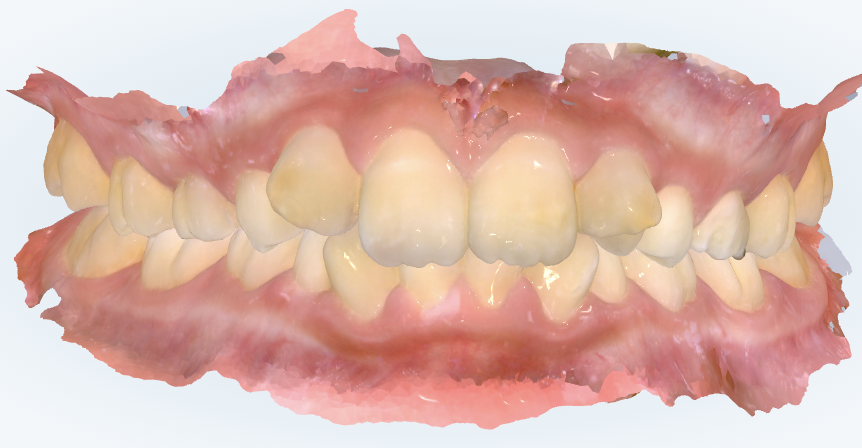

初診時の画像診断

上下の歯並びにガタガタがあります。

ガタガタが気になるとの事ですが、ガタガタは“すごく目立つ”わけではないですが、口の中を見ると重なりは大きいですね。歯の半分くらい重なっているところもあります。

今回の診察では、見た目として歯の重なりが大きく、今後の生え変わりの進行によってさらに歯が生えるスペース不足が顕在化する可能性がある点を丁寧にご説明しました。また、CT所見からは骨格的な大きな異常は認めにくく、永久歯の本数も揃っていることが確認できたため、“成長を利用してスペースを作る”ことが最も合理的な治療方針であると判断しました。